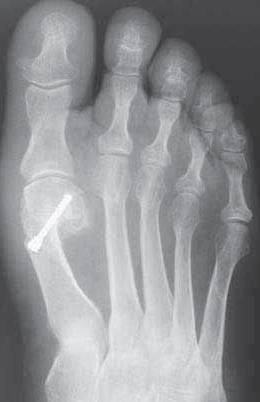

Η διάγνωση επιβεβαιώνεται με την σωστή κλινική εξέταση και την φόρτιση του γυμνού ποδιού στο πάτωμα στο ιατρείο μαζί πάντα με ακτινογραφία που φέρει ο ασθενής συγκριτική και των δύο ποδιών πάνω στην ίδια ακτινολογική πλάκα με φόρτιση , δηλαδή όρθιος με όλο το βάρος του σώματος. Αυτό διότι χρειάζεται να μετρηθούν οι γωνίες του ποδιού και των μεταταρσίων για να διαπιστωθεί ποιό είναι το αίτιο που οδήγησε στην παραμόρφωση και στο κότσι.

Η θεραπεία σε μετρίου και μεγάλου βαθμού παραμορφώσεις είναι χειρουργική . Αυτό σημαίνει ότι μέσα από μικρές τομές γινεται οστεοτομία στο 1ο μετατάρσιο ακριβώς στο σημείο που χρειάζεται ( στην βάση , διάφυση ή περιφερικά ) αναλόγος με το που υπάρχει τοαίτιο που δημιούργησε το κότσι . Η οστεοτομία σταθεροποιείται με βίδες ή όταν χρειάζεται με ειδική ανατομική πλάκα . Όλο το χειρουργείο είναι αναίμακτο λόγω ίσχαιμου περίδεσης στο πόδι κατά την διάρκεια της επέμβασης . Μπορεί να γίνει με μπλόκ των νεύρων στην οπίσθια επιφάνεια του γόνατος ή στο επίπεδο του αστραγάλου . Συνήθως η επέμβαση γίνεται ώς ημερήσια νοσηλεία ένω σε πιό μεγάλες διορθώσεις ο ασθενής μπορεί να πάρει εξιτήριο την επόμενη μέρα το πρωί .

Η διεθνής βιβλιογραφία περιγράφει πάνω από 100 διαφορετικές επεμβάσεις για την διόρθωση του βλαισού μεγάλου δακτύλου και δεν είναι απλή υπόθεση . Χρειάζεται ένα πολύ καλό εξατομικευμένο προεγχειτητικό πλάνο για να βρεθεί ακριβώς που έγκειται το πρόβλημα , έτσι ώστε το κατάλληλο χειρουργείο να οδηγήσει σε ένα πολύ καλό αποτέλεσμα χωρίς υποτροπή στο μέλλον.